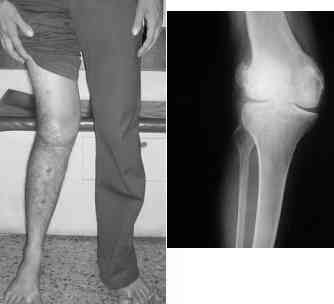

This 20 year old patient sustained a fracture in the lower end of the femur, one and a half years ago, with a compound wound over the fracture area. Notes at that time mention a compound fracture dislocation, with a loss of part of the lateral condyle. This was treated by debridement, and external fixation. After two weeks, the lateral condyle (coronal fracture) was fixed by a screw and k wire in an AP direction.

At present, he has a valgus deformity of the knee, with 0-45 degrees of movt. The knee is stable to examination, could not be corrected to neutral from the existing valgus, and despite the deformity he is walking on it, albeit with pain and some difficulty.

He was referred to me for correction of his deformity.